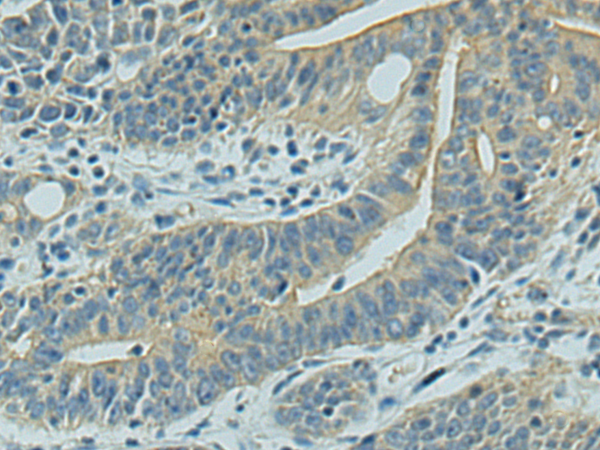

IHC positive control: |

Human gastric cancer and Human tonsil |

IHC Recommend dilution: |

150-300 |